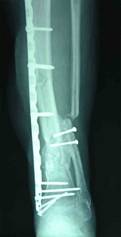

患者2年前因车祸导致左胫腓骨开放粉碎骨折,进行钢板内固定手术,术后伤口感染,钢板和骨外露。经过皮瓣移植伤口愈合,小腿大片贴骨瘢痕。足部皮温低,足背动脉触摸不清。X线片显示胫骨腓骨骨折钢板内固定,胫骨骨折不愈合,形成骨缺损,断端硬化。

X线片显示胫骨腓骨骨折钢板内固定,胫骨骨折不愈合,形成骨缺损,断端硬化。胫骨钢板螺丝钉已经有松动迹象。